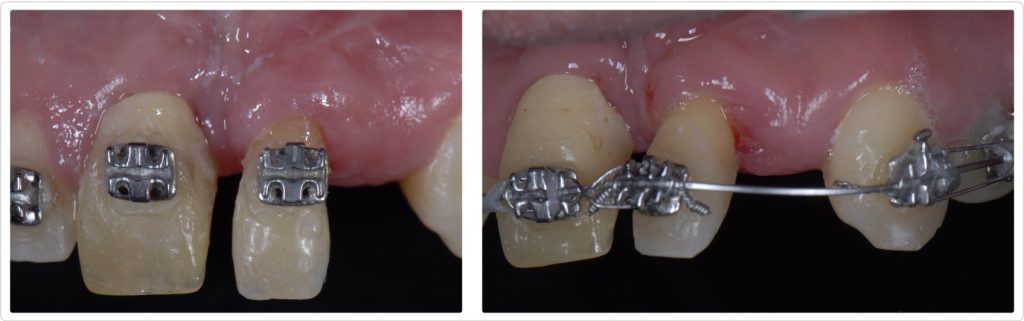

Adjunctive orthodontic therapy

Both treatment options were presented to the patient during a thorough discussion that helped him understand their implications. During the conversation, another important challenge involved with the AOT alternative was highlighted: managing the space created during the orthodontic phase before implant placement.

Fortunately, the patient insisted on the most structurally and biomechanically sound solution. Accordingly, the team proposed performing AOT as a proven, predictable means of getting optimal hard and soft tissue volume, instead of performing additional bone and soft tissue grafts.

The orthodontic therapy (Figs. 9 and 10) took nearly a year, and luckily the patient adhered to our recommendations and home care (which can be problematic with some patients). Once the ortho was finalized, we extracted the lateral incisor, placed two osseointegrated implants using a restrictive surgical template, and then restored them (Figs. 11 and 12).